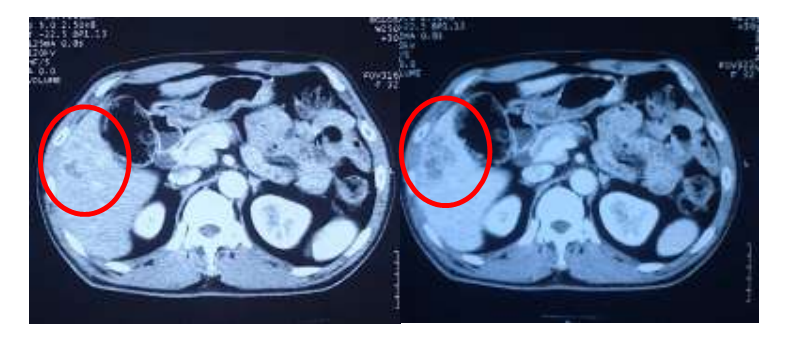

Chụp cắt lớp vi tính ổ bụng: Hình ảnh khối nhu mô gan hạ phân thùy V gan phải kích thước 25×36 mm, sau tiêm ngấm thuốc. U đại tràng sigma kèm hạch vùng lân cận

Hình 1: Hình ảnh khối nhu mô gan hạ phân thùy V gan phải kích thước 25×36 mm, sau tiêm ngấm thuốc (vòng tròn đỏ)